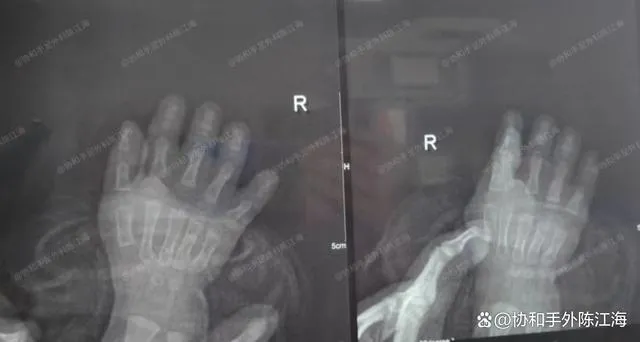

tia X

Đứa trẻ này mắc hội chứng Ba Lan, một dị tật khá độc đáo, đặc trưng bởi cả đặc điểm ngắn và dính ngón (ngón tay có màng), ảnh hưởng đáng kể đến cả hình dáng và chức năng. Khi được 11 tháng tuổi, đứa trẻ đã được phẫu thuật. Trong lần theo dõi này khi được 2 tuổi rưỡi, bàn tay của cô đã lớn hơn đáng kể và giờ đây cô có thể cầm nắm những vật thể lớn hơn.